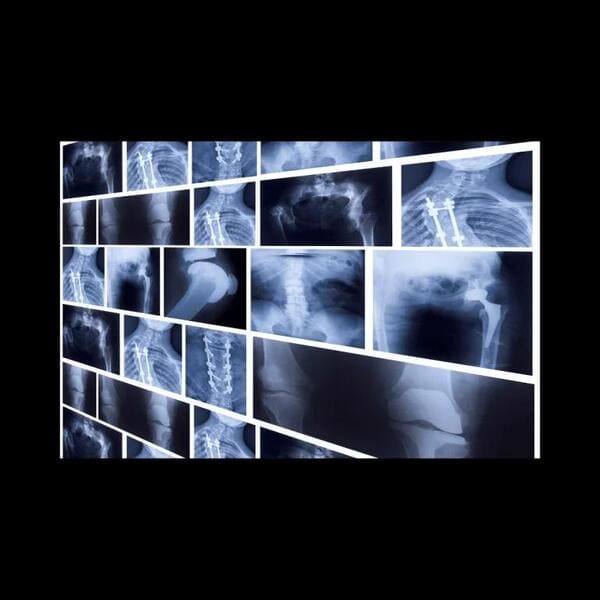

🔶手術

重度の骨折は整復してもすぐに元に戻ってしまうため手術を行います。手術的治療にはいくつかの方法がありますが、骨折の状態や折れた部位などから総合的に判断されます。